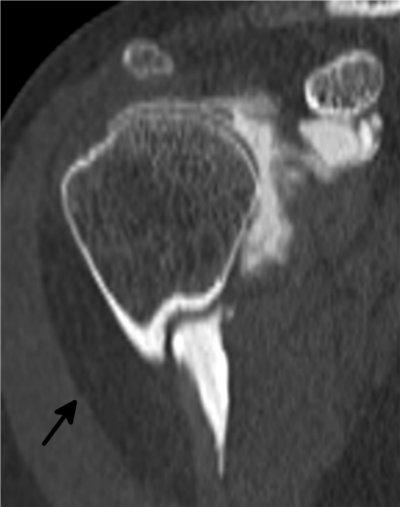

Capsulite rétractile arthrographie (images 1 et 2)

Arthroscanner correspondant (images 3 et 4)